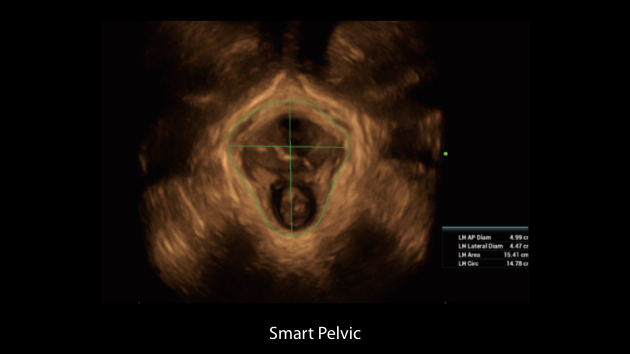

Scenario-oriented Full-stack Intelligence

The innovative Smart Scene 3D solution enables automated identification of tissue characteristics and delivers organ-specific diagnosis with full-stack intelligence throughout the entire procedure. This innovation reduces dependence on clinical skills, while elevating diagnostic accuracy, confidence, and efficiency.